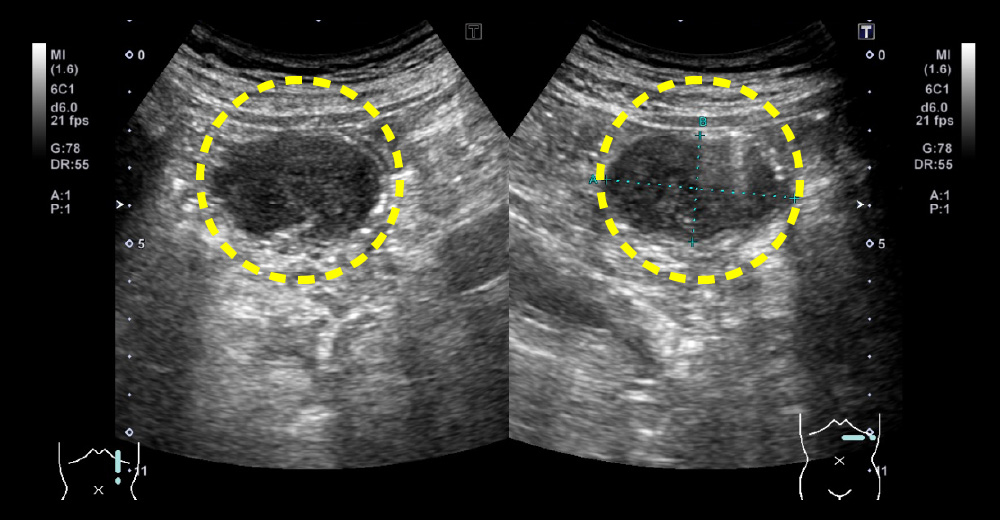

糖尿病の脂肪肝(MAFLD)、肝がんサーベイランスにおける定期腹部エコーで診断された無症状空腸GISTの患者さんです。

無症状空腸GIST 無症状空腸GIST

無症状空腸GIST